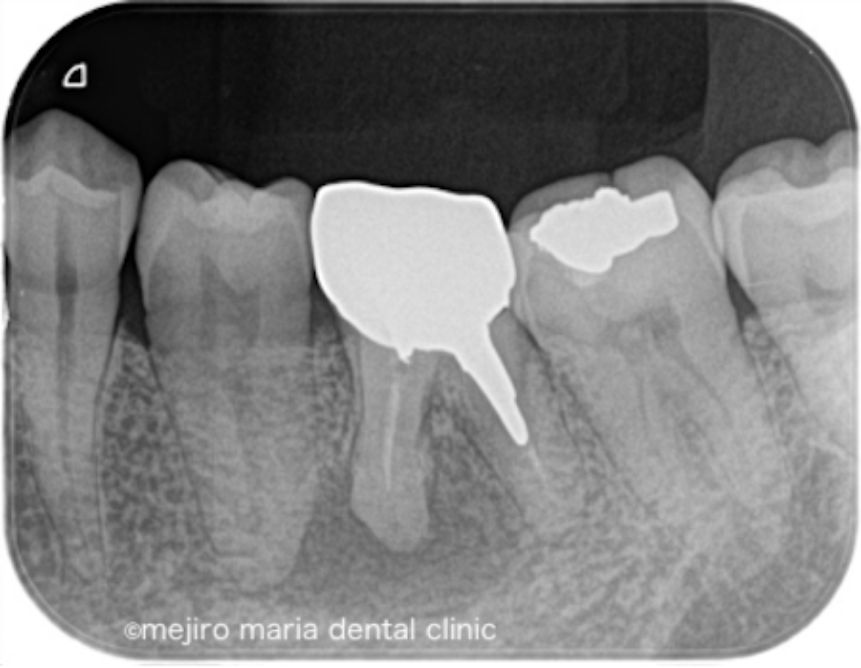

治療前の状態・主訴

今回の症例は10年以上の間フィステル(瘻孔)がある状態で放置したケースです。患者様はそもそも歯科治療に恐怖心があり、歯ぐきにできたフィステルが悪いものと診断されることが怖く、歯科治療から遠ざかっておられました。

最近になって痛みを伴う腫れが頻繁に発症するようになったことに耐え難くなり、当院を受診されました。

当院を受診する前にも根管治療を行なっている歯科医院を受診するも、抜歯しインプラントを勧められたとのことでした。当院の診査では抜歯をするほどの所見は確認できず、通常通りの精密根管治療を行うことをご提案させていただきました。